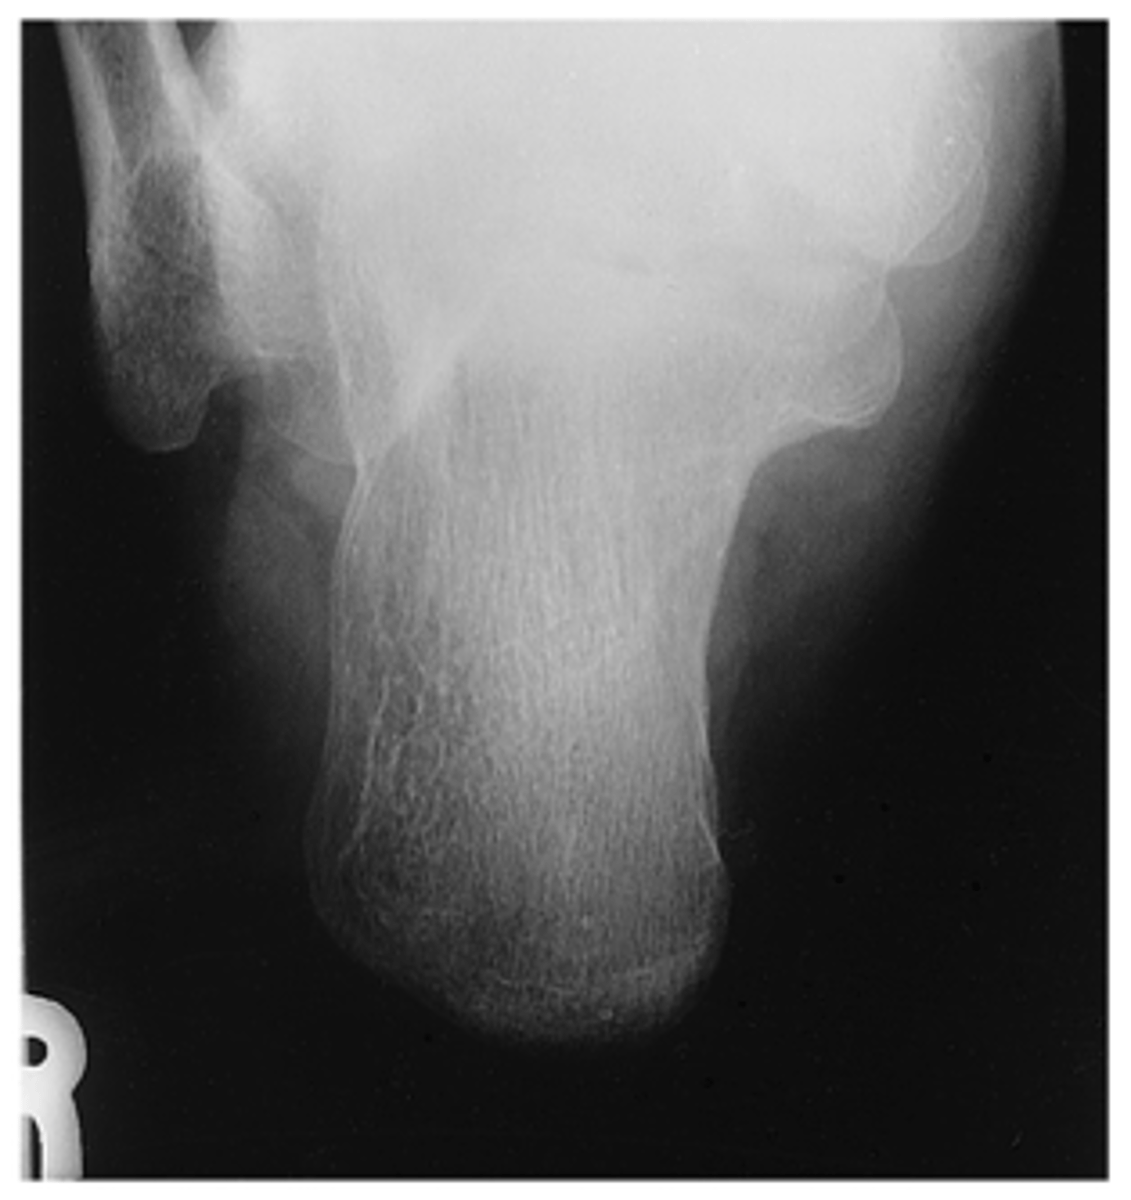

Plantodorsal (Axial) Calcaneus

What projection is this?

Evaluation Criteria Plantodorsal (Axial) Calcaneus

- CR 40° to cephalad

- CR to base of third MT to emerge posterior to malleoli

- Entire calcaneus visualized

- No rotation

- Optimal exposure factors